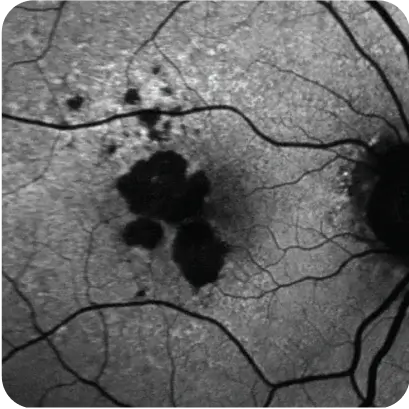

What may be happening to the retina and your patient's vision7

What may be happening to the retina

What may be happening to your patient's vision7

Loss of peripheral, low‑light vision; patches of central vision loss

Representation of vision loss for illustrative purposes only.

Images courtesy of Heidelberg Engineering, Dr. Julie Rodman, and Dr. Mohammad Rafieetary.